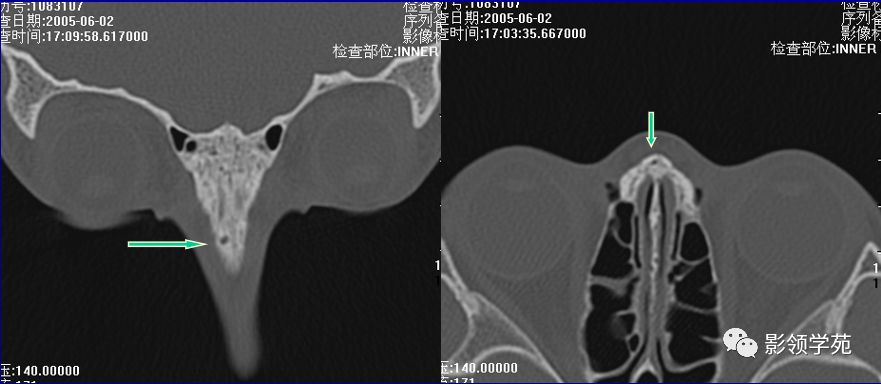

右侧鼻骨线形骨折

鼻骨线形骨折

左侧鼻骨线形骨折

右侧鼻骨骨折

左上颌骨额突骨折